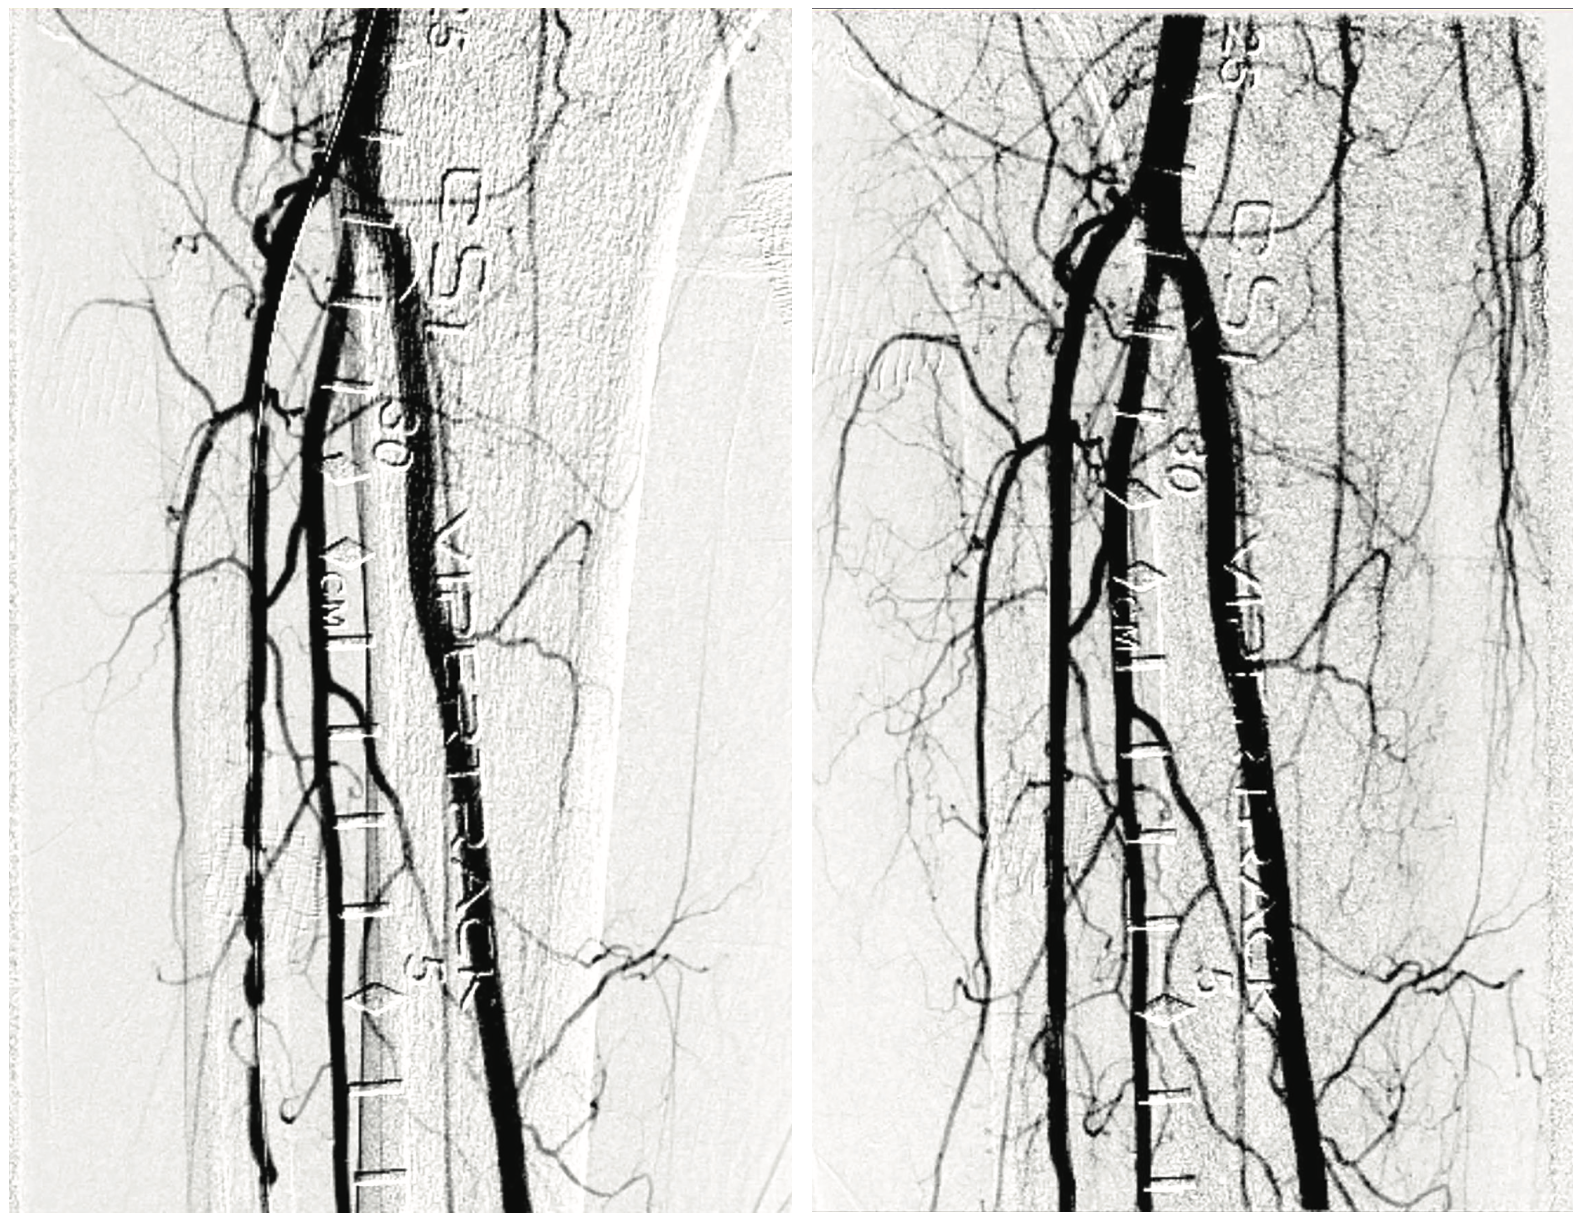

In vessels with multiple tandem lesions with segments of normal vessel, a differential balloon expansion can cause flow-limiting dissections. That is where the design of the Highlander™ 014 PTA Balloon becomes important. The balloon maintains highly precise sizing relative to its labeled diameter, even at inflation pressures up to 30 atmospheres. In my practice, I have found that the Highlander™ 014 PTA Balloon Dilatation Catheter works well in the type of non-focal lesions we typically see in our below-knee interventions, which is why we prefer it as one of our treatment modalities.

Since we are a referral center, we see a lot of complex cases. We typically find more diffuse lesions, and the idea is to prep the vessel to increase the patency and outflow. If it is a long, diffuse lesion with areas of abnormal and normal segments, the Highlander™ 014 PTA Balloon Dilatation Catheter has helped us to expand the lesion well, providing adequate pressure for expansion at the tightest area of the lesion, while at the same time causing minimal trauma to the normal segments. In expanding the lesion, we want to cause controlled, non-flow-limiting dissection and increase the luminal gain, thereby helping with the patency and other PAD symptoms the patient is suffering from, all the way from rest pain to wound healing.